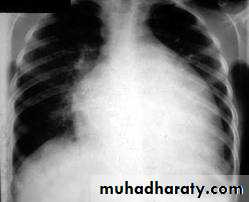

A- CHEST- CXR: 1-cardiomegaly with clear lung2-Pulmonary venous congestion

3-Pulmonary edema

#CXR- may be normal ,cardiomegaly ,pulmonary congestion